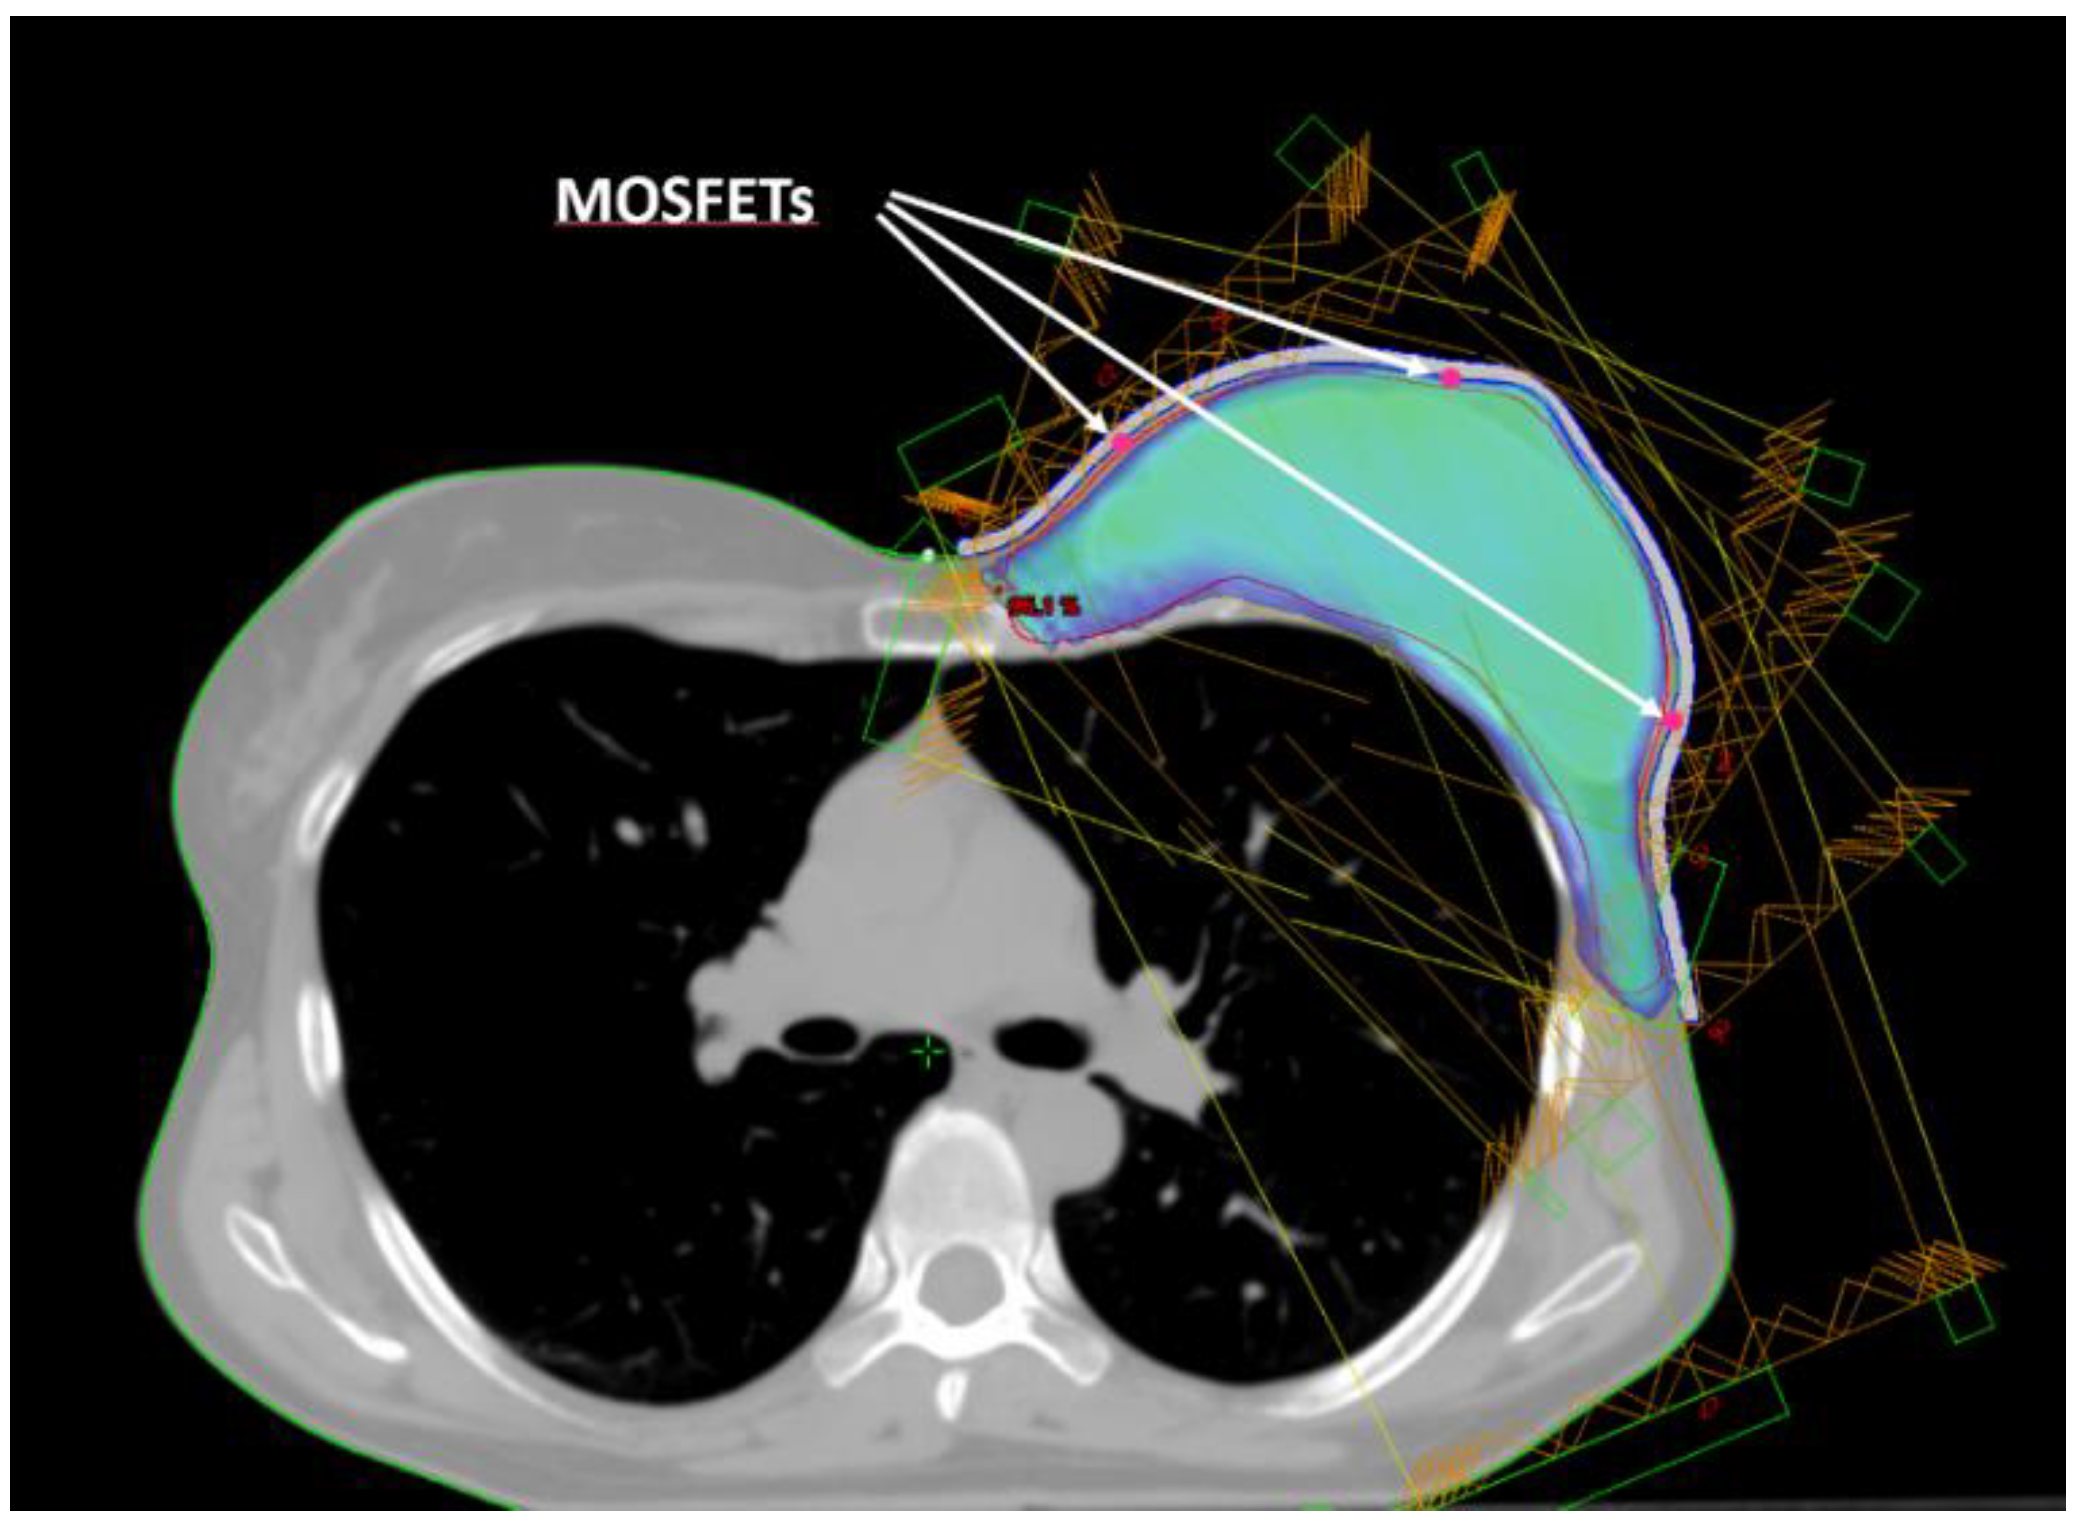

Five small spherical ROIs were contoured at positions where the skin point dose will be evaluated. The five ROIs were subtracted from the inner surface of the bolus ROI and used to create a suitable housing for MOSFET dosimeters positioning (Figure 2). Thus, for the following dosimetric evaluation the position of the MOSFETs inside the printed bolus corresponded to the ROIs contoured on the TPS.

Figure 2. Beam arrangement for IMRT dose delivery. Isodose of 95% of prescribed dose. Positions of the three middle height MOSFETs.